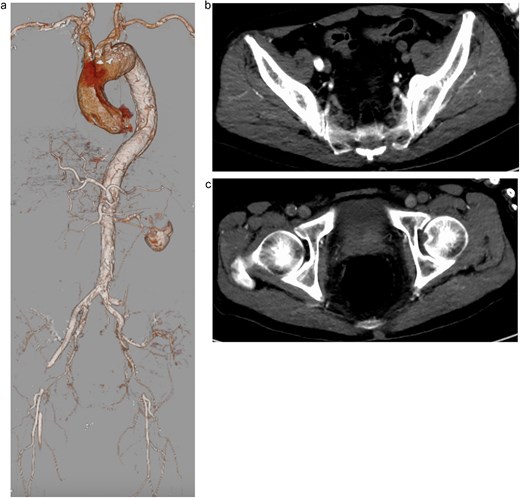

The patient was extubated on postoperative day (POD) 3, and neurological examination revealed no abnormalities, with intact motor and sensory function in the lower limbs. To prevent MNMS, continuous renal replacement therapy (CRRT) was initiated immediately after surgery. Although MNMS was successfully avoided, renal dysfunction persisted, requiring temporary dialysis until POD 19. At the last follow-up, renal function had improved to preoperative levels, with a serum creatinine of 1.96 mg/dl and an estimated glomerular filtration rate of 26.9 ml/min/1.73 m2. Postoperative CT imaging revealed occlusion of the Ao-F bypass due to expansion of the true lumen; however, perfusion of the lower limbs and the right kidney, which had been malperfused preoperatively, was well preserved (Fig. 2).

Postoperative contrast-enhanced 3D computed tomography demonstrating successful total arch replacement with frozen elephant trunk insertion and ascending aorta-to-bilateral femoral artery (Ao-F) bypass. Although the Ao-F bypass graft is occluded, lower limb perfusion is preserved via expansion of the true lumen following central repair.